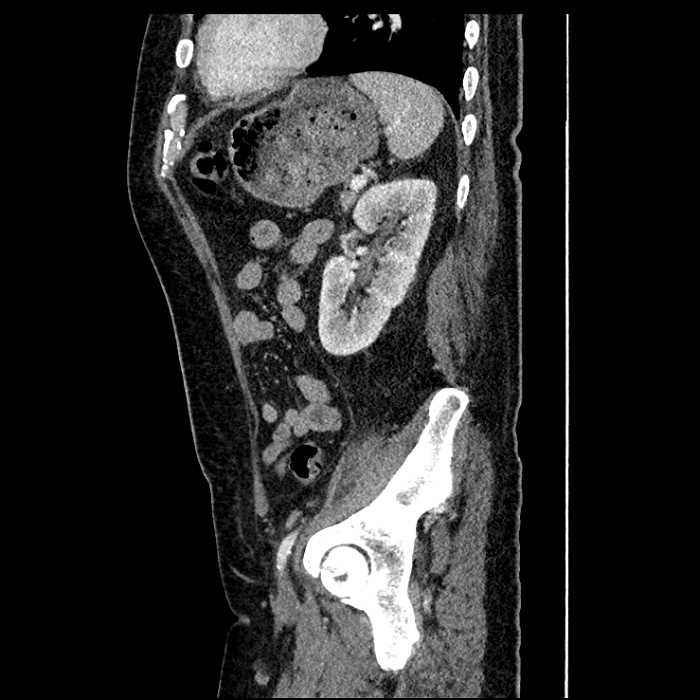

Age: 63

Sex: Male

Indication: Abdominal pain

• Large fluid density structure in hepatic segments 7 and 8 measuring 10 x 7 x 7 cm with internal septation and circumferential ill-defined low density compatible with edema

• Peripherally enhancing subcapsular collections along the anterior margin of the left hepatic lobe measuring 3 x 1 cm and 2 x 1 cm

• Clearly marginated fluid density structure in segment 7 and several other scattered tiny hypodensities, which likely represent cysts

• Mild mural thickening of a segment of the sigmoid colon with adjacent fat stranding and a 1.5 cm fluid and gas collection along the tip of an inflamed diverticulum

• Loss of the normal fat plane between this collection and adjacent loops of small bowel, which demonstrate mural thickening

Acute sigmoid diverticulitis complicated by a small contained perforation and a large abscess in the right hepatic lobe. Additional small subcapsular abscesses along the anterior margin of the left hepatic lobe.

Additionally, loss of the normal fat plane between the peridiverticular collection and adjacent thickened loops of small bowel raises the potential for an enterocolonic fistula.

• The classic CT imaging appearance is a double target sign with internal low density surrounded by an internal enhancing rim (capsule) and a low density external rim (edema)

Hepatic abscess showing the double target sign with low density internally surrounded by a thin inner enhancing rim (red arrow) and ill-defined outer low density rim (yellow arrow). Blue arrow indicates an internal septation. Red arrows: additional smaller subcapsular abscesses. Red arrow: focal contained perforation associated with diverticulitis.